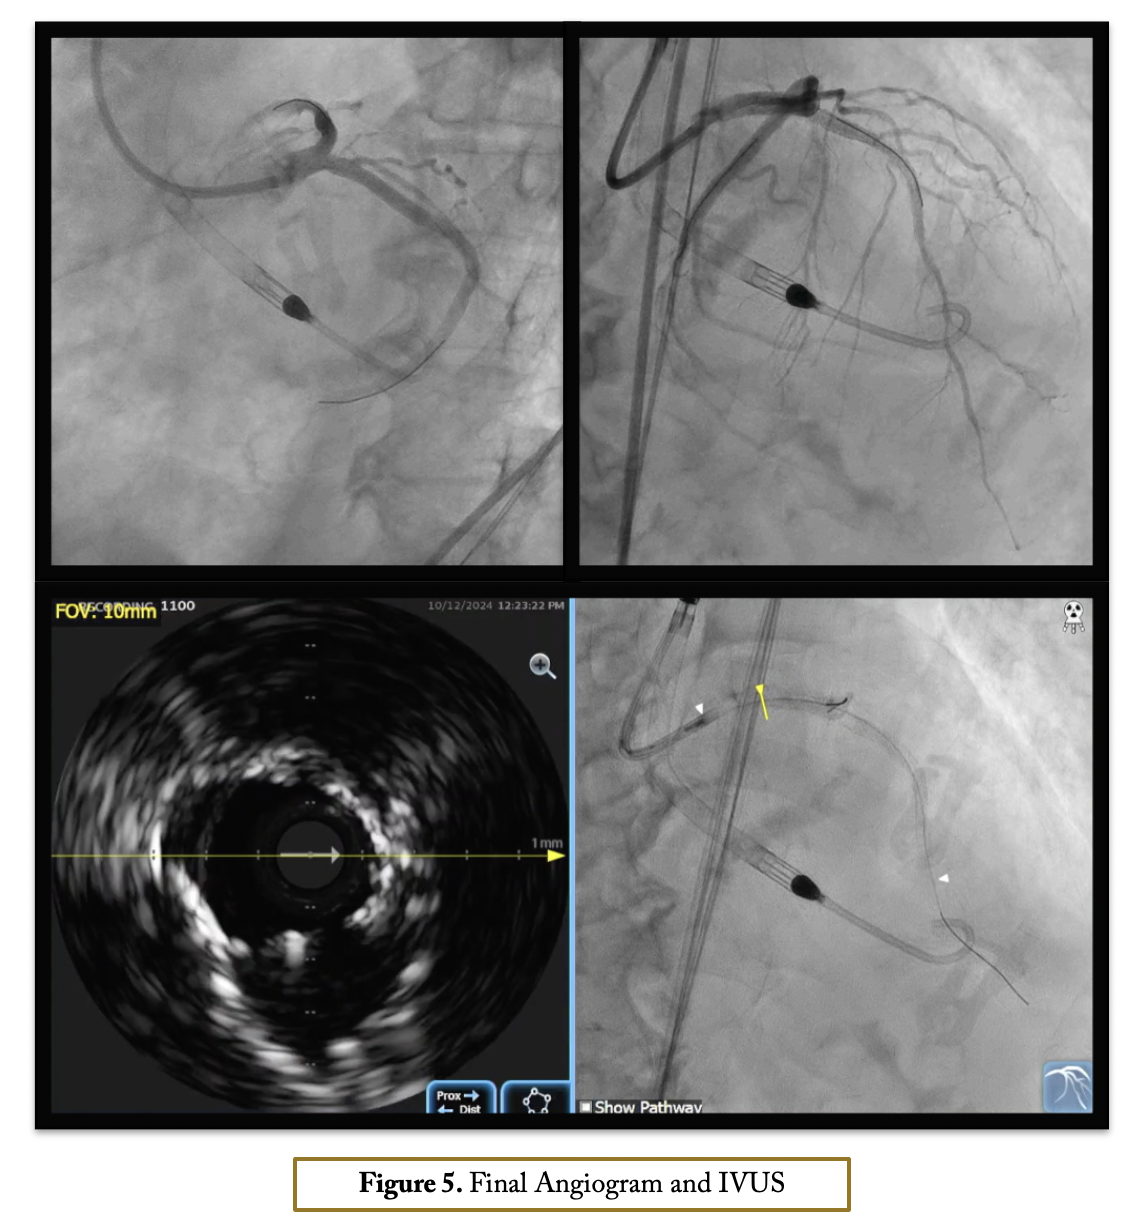

After confirming iliofemoral anatomy suitability for Impella via intravascular ultrasound (IVUS), right femoral access was obtained with a 14-Fr introducer and two suture-mediated closure devices. Diagnostic angiogram views were set as static monitor images. A 7-Fr sheath was inserted through the Impella introducer, and an EBU 3.5 7-Fr guide catheter engaged the left main coronary without contrast, aided by pressure damping, calcification identification, ECG changes, and wire probing. Co-registration with IVUS was performed using the Eagle Eye IVUS catheter, the only device compatible with the Syncvision co-registration system. IVUS imaging of the left main-LAD revealed fibrocalcific plaque with up to 360-degree calcification in the LM-LAD and LCx. Stent landing zones and vessel sizes were identified, and IVUS imaging of the LCx confirmed severe ostial disease. Rotational atherectomy was done with a 1.5 mm burr in both LAD and LCx. Intravascular lithotripsy (IVL) with a 4.0 mm balloon was applied in the ostial LCx and LM with 120 pulses. The LM bifurcation was treated with a DK crush technique with a non-polymer-jacketed wire is looped in the aortic root to prevent guide catheter engagement in the LM, allowing ostium identification without contrast Final IVUS and angiogram showed good outcomes with stable hemodynamics via Impella support. Hemostasis was achieved with Proglide sutures after device removal.